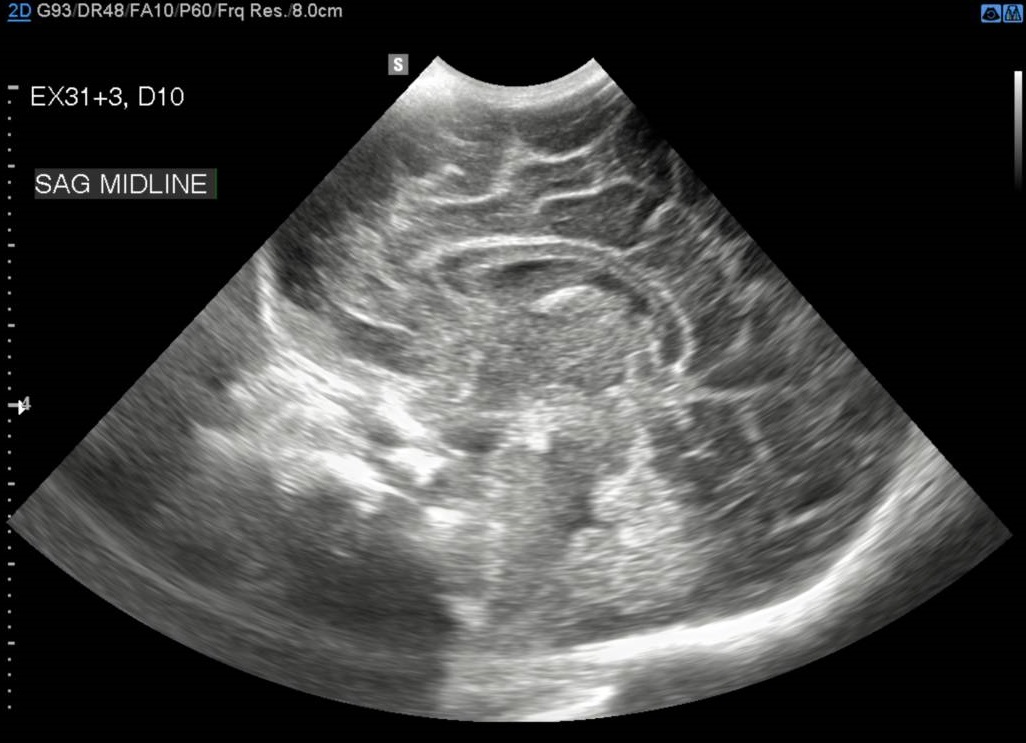

These key documents outline the NICU PoCUS program policy, structure, training and credentialing requirements. The cranial ultrasound images required are 4 coronal and 3 sagittal images.